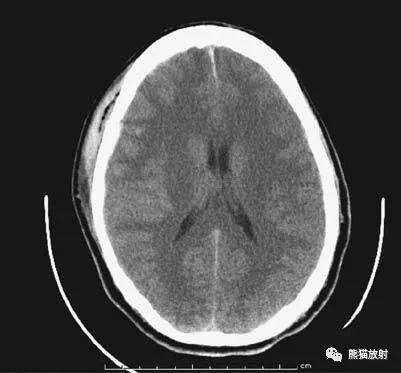

做一个头部ct需要多少钱

医院等级医院的等级也是影响费用的重要因素高级别的医院,如三甲医院,由于设备更先进技术更专业,因此收费也会相对较高二检查部位决定费用 不同部位价格不同CT检查的费用还取决于检查的具体部位例如,头部CT的费用估计在400...